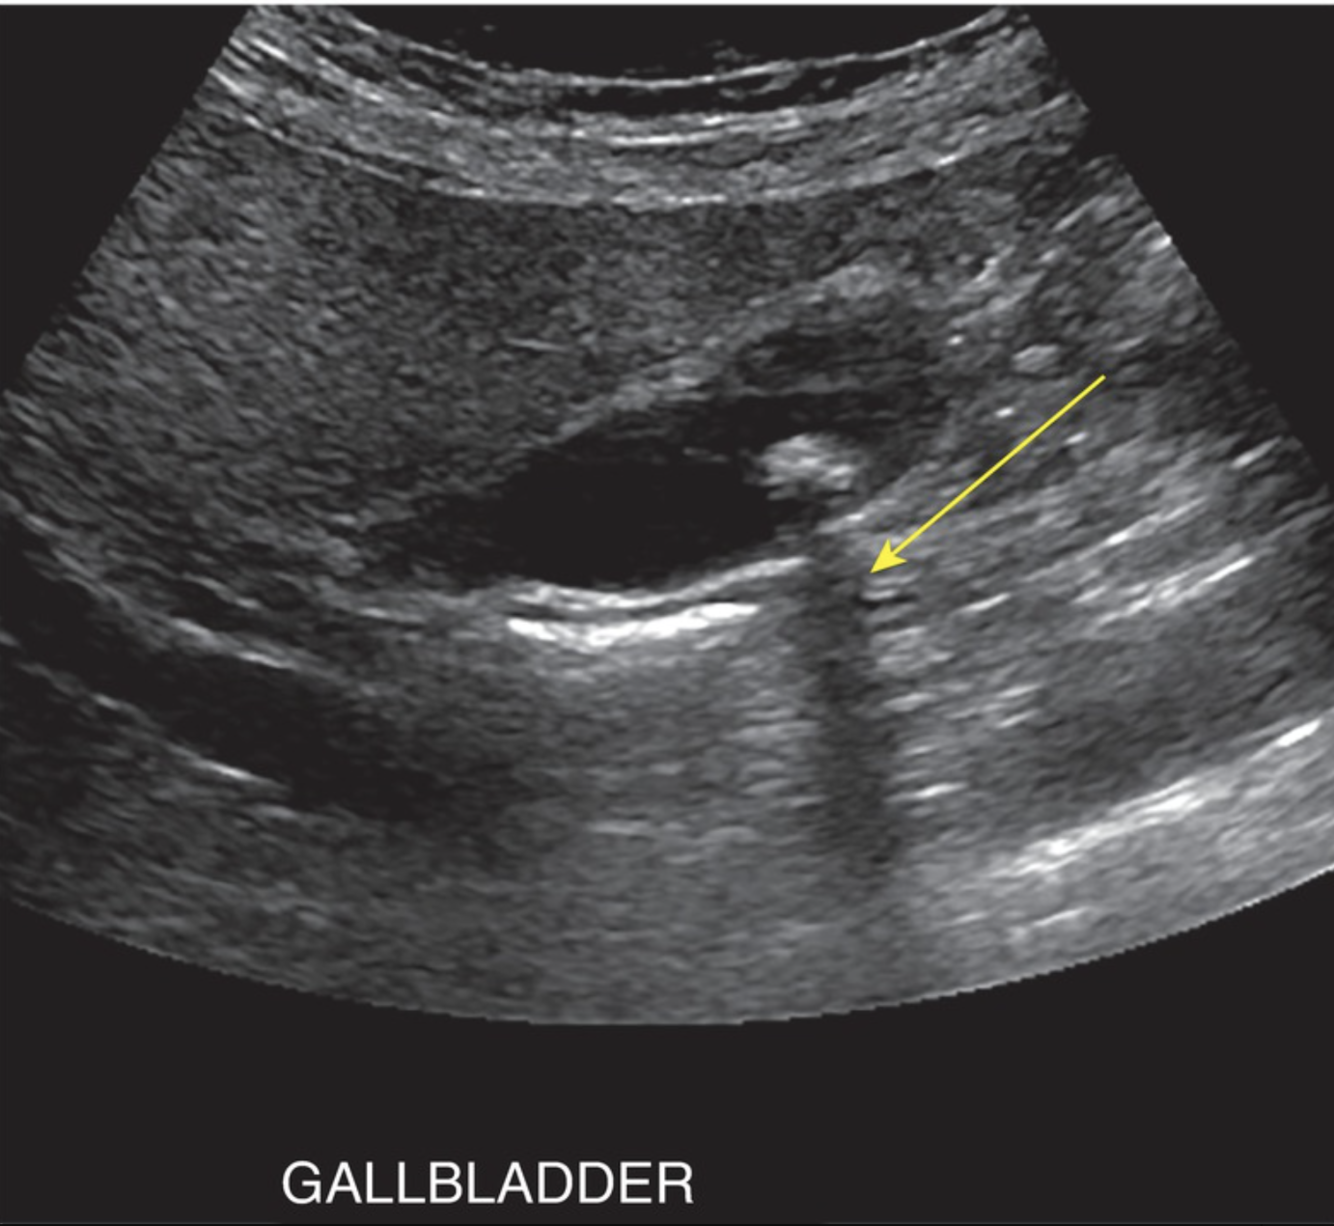

Which phenomenon is responsible for the following US artifact?